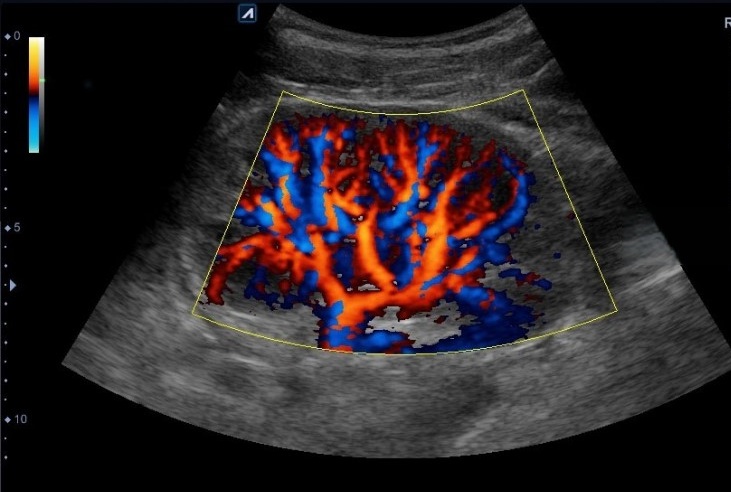

Допплерография используется для визуализации и оценки кровотока в почечных сосудах.

- Сосуды почек. Диагностика кровотока в артериях. Исследование вен для оценки их текущего состояния.

- Кровоток. Его скорость в почечных артериях, венах.

- Диаметр сосудов. Допплерография предоставляет врачу (через визуализацию) дополнительную информацию о текущем состоянии сосудистой системы почек (диагностика венозного оттока, процент сужения артерий).

УЗДГ дает возможность врачу визуализировать:

- недостаток кровоснабжения почек, скорость кровотока в сосудах;